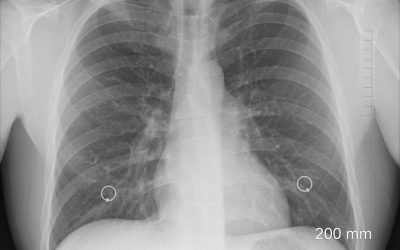

LONG-TERM MASK USE MAY CONTRIBUTE TO ADVANCED STAGE LUNG CANCER, STUDY FINDS

LONG-TERM MASK USE MAY CONTRIBUTE TO ADVANCED STAGE LUNG CANCER, STUDY FINDS By PHILLIP SCHNEIDER - BLN STAFF WRITER www.blacklistednews.com A recent study in the journal Cancer Discovery found that inhalation of harmful microbes can contribute to advanced stage lung cancer in...